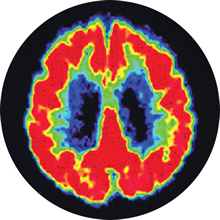

Using brain scanning techniques, such as positron emission tomography (PET), researchers have discovered something else in the brains of people with Alzheimer’s:

Normal cerebral

glucose metabolism

Image source: Small GW, Ercoli LM, Silverman DHS, et al. Cerebral metabolic and cognitive decline in persons at genetic risk for Alzheimer's disease. Proc Natl Acad Sci USA. 2000;97(11):6037-6042. Copyright 2013 National Academy of Sciences, U.S.A.

- Diminished cerebral glucose metabolism – or glucose hypometabolism, means that neurons have difficulty producing the energy they need to function. Neurons normally use glucose (a type of sugar) as the primary fuel source to power the brain’s daily activities. In Alzheimer’s disease, scientists have discovered that the engines inside neurons malfunction, so that even if there is enough glucose in the body, the brain cannot use it properly. This most often occurs in the areas of the brain involved in memory and cognition, and it can begin years, sometimes decades, before any symptoms of the disease appear